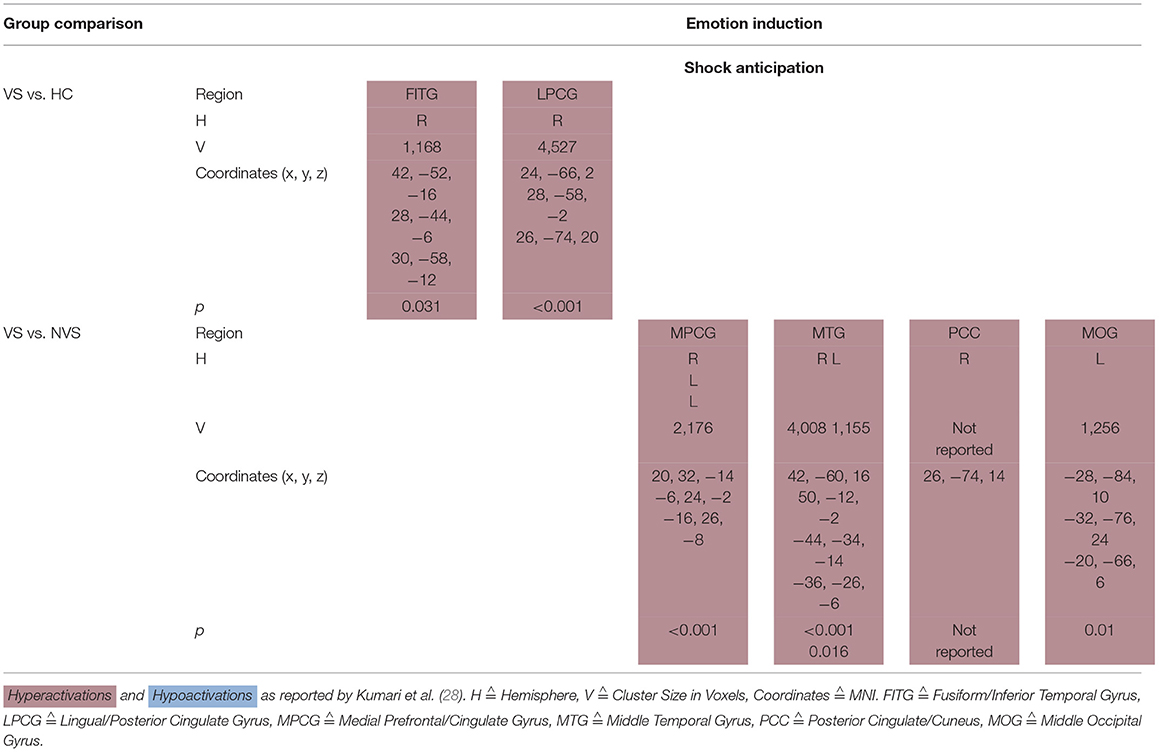

Shock Anticipation

Kumari et al. (28) conducted a fMRI study where participants (VS, NVS and HC) were threatened to receive an electric shock. Under shock anticipation, VS as opposed to HC hyperactivated the right fusiform/inferior temporal gyrus as well as the right lingual/posterior cingulate gyrus.

VS vs. NVS hyperactivated the medial prefrontal/cingulate gyrus bilaterally, middle temporal gyrus bilaterally, right posterior cingulate/cuneus, and left middle occipital gyrus (see Table 5A).

Shock Anticipation

Kumari et al. (28) found that when anticipating electric shock, violent persons with schizophrenia as opposed to HC show hyperactivations in right fusiform/inferior temporal gyrus as well as in right lingual/posterior cingulate gyrus.

When comparing violent with non-violent persons with schizophrenia under shock anticipation, violent persons with schizophrenia hyperactivated their medial prefrontal/cingulate gyrus bilaterally, middle temporal gyrus bilaterally, right posterior cingulate/cuneus, and left middle occipital gyrus.

Concluding, the AC, medial/inferior frontal regions, insula, striatum, and temporal regions were activated during anticipatory fear. These results are in line with a previous study by Chua et al. (60). The cingulate cortex and the insula are activated during emotional recall/imagery (61), while the neural representation of fear has been hypothesized to be located in the AC/medial prefrontal cortex (62).